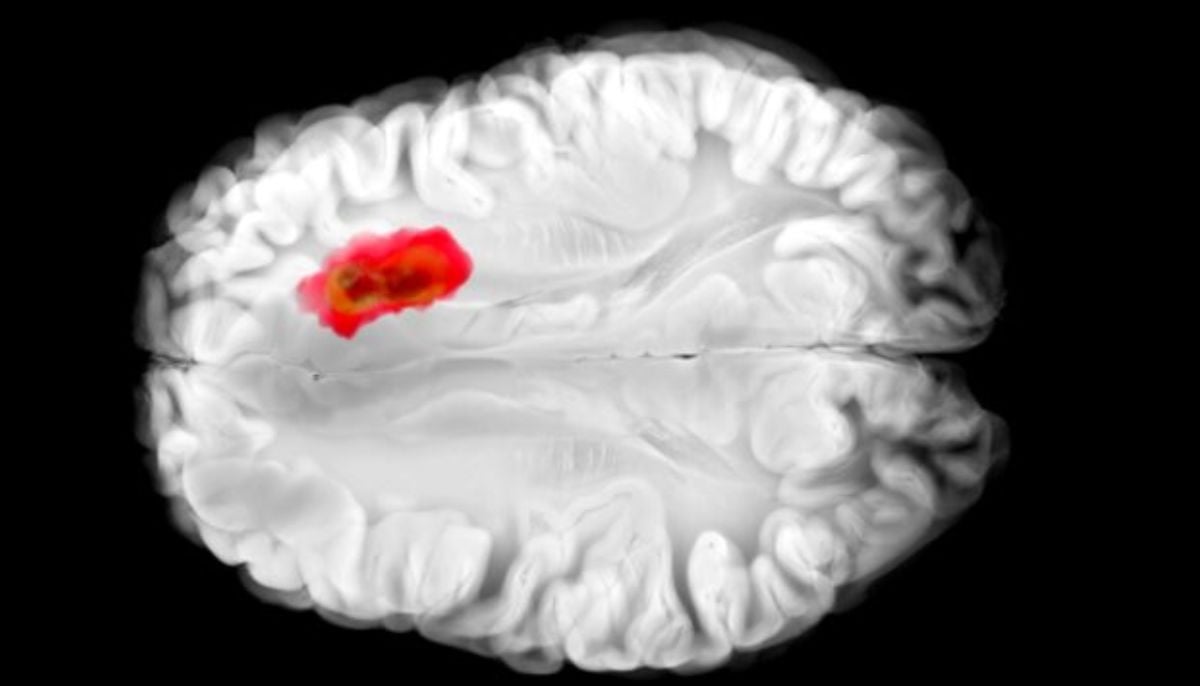

Researchers found that RSV infection with Respiratory Syncytial Virus may set the stage for asthma in children, because the virus appears to trick the developing immune system into exaggerated responses to everyday allergens.

Quoting one, he said: “We found that RSV infection in early life and the risk of genetic allergy interact in a very specific way, pushing the immune system toward asthma.”

To evaluate the process, the researchers combined national health registry information from all children from Denmark with controlled laboratory studies and revealed how an early viral infection can increase the impact of hereditary allergy risk.

Belgian researchers from VIB and Ghent University have found strong evidence that RSV infection in young children can develop childhood asthma, especially in children with a family history of allergies, because the allergen-specific antibodies passed from parents to their newborns act more quickly.